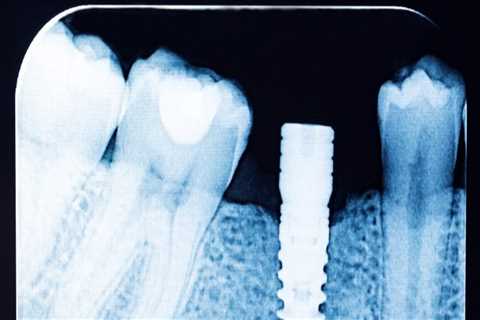

How Dental X-Rays Influence Treatment Planning for Implants and Orthodontics

Dental X-rays have revolutionized modern dentistry by allowing professionals to see what the naked..